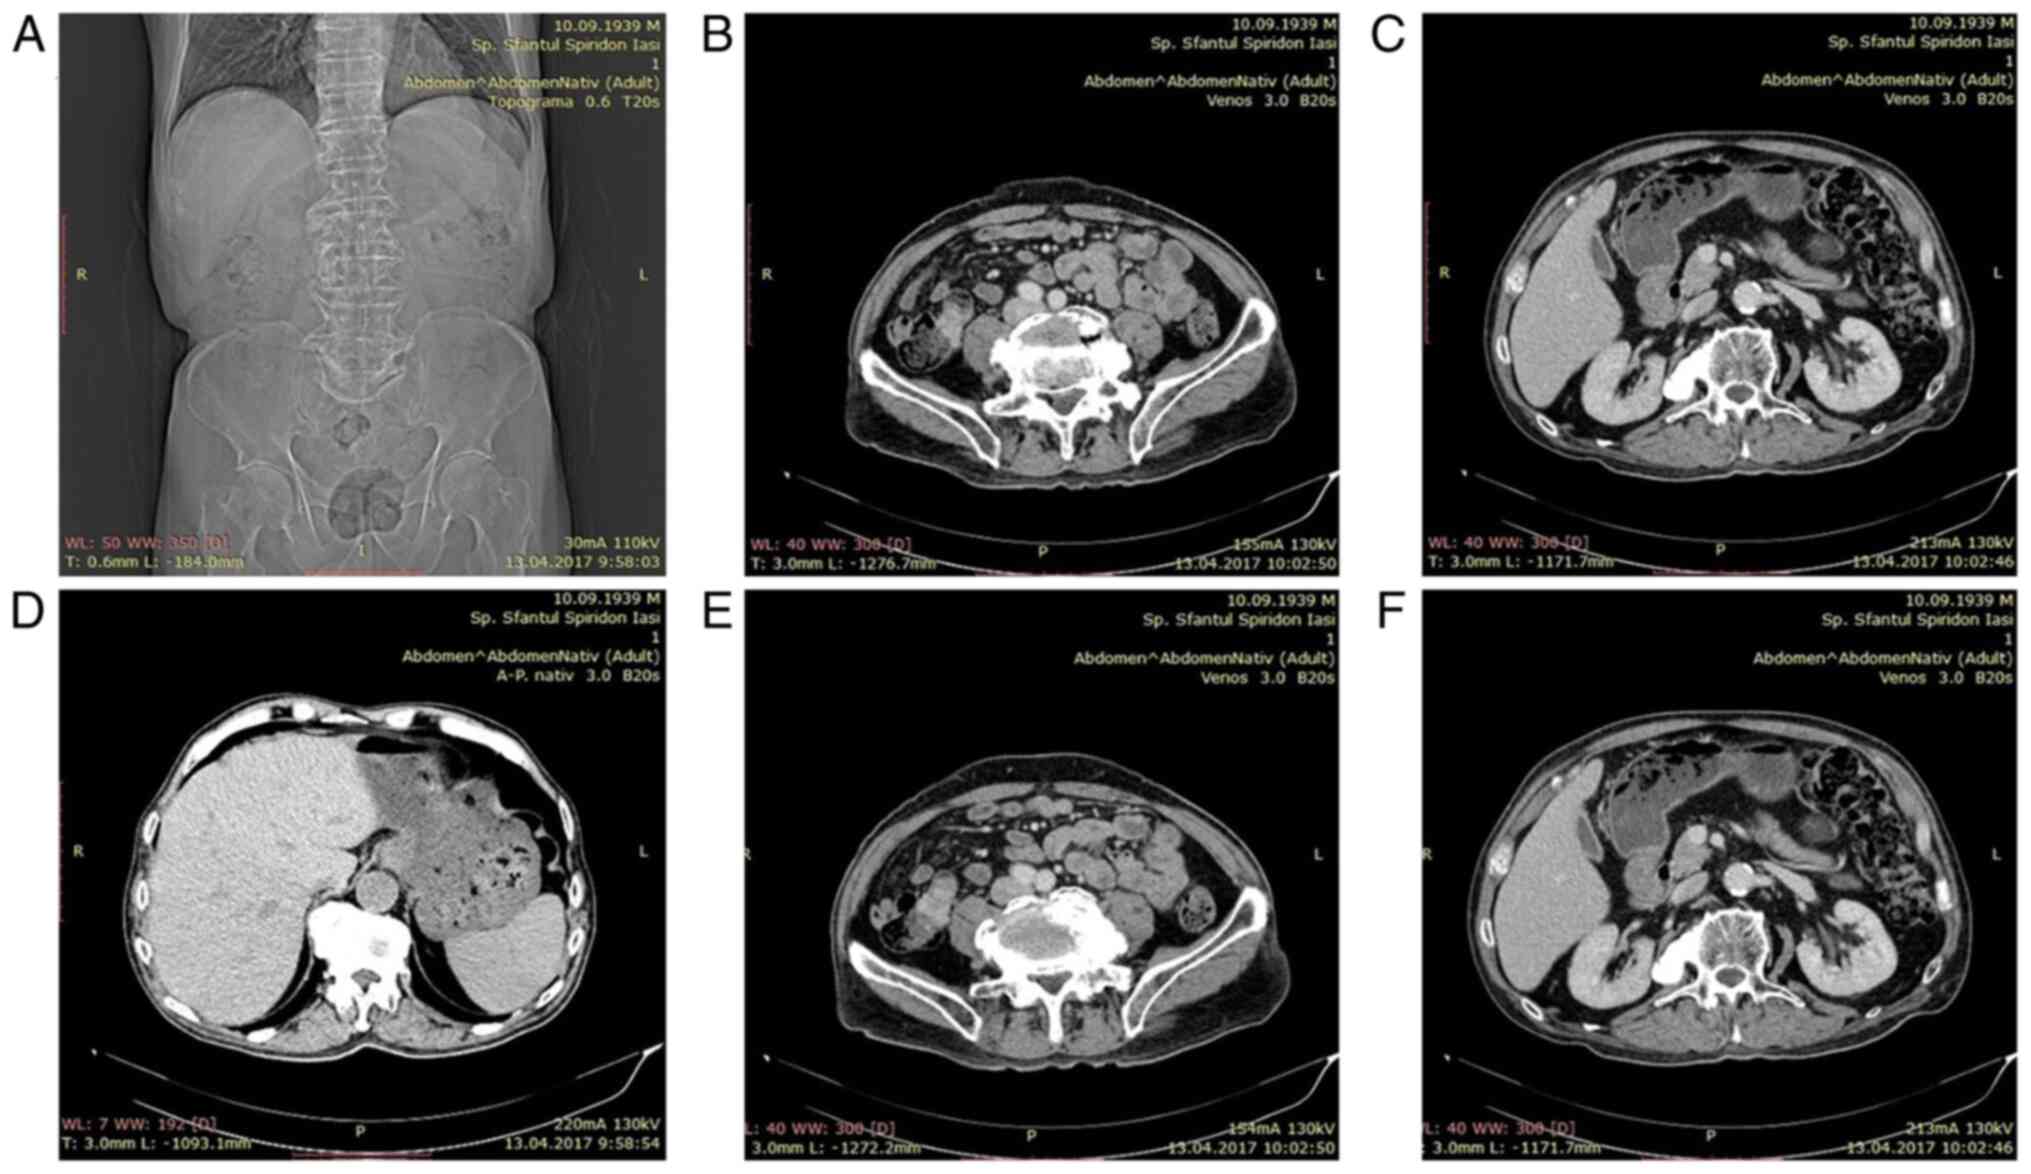

The patient's status declined within a week, leading to systemic steroid being added to the medication. Considering that the patient's progress was unfavorable in the subsequent days, and the small intestine was not investigated, an abdominal and pelvic computed tomography (CT) scan was performed showing a tumoral mass located in the small bowel on the terminal ileum (Fig. 5).

Figure 5

(A-F) Abdominal CT scan showing a mass on the terminal ileum of the small bowel.

CT is the imaging scan that can guide the diagnosis of NETs in the small intestine (18). CT detection sensitivity for NETs in the small bowel is from 7 to 38%. The sensitivity can reach to 82% if the presence of mesenteric lymphadenopathy/fibrosis is interpreted (19).